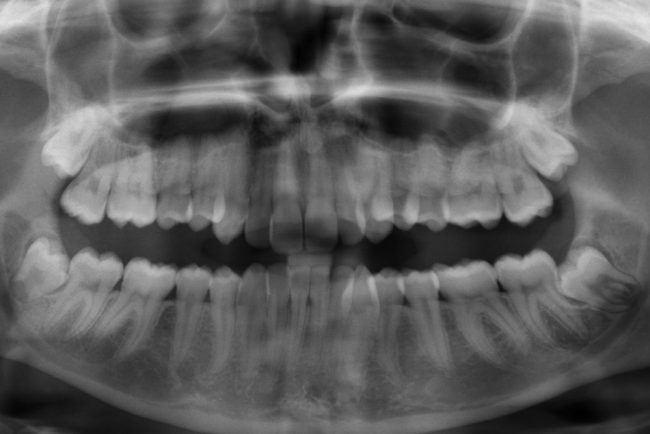

Röntgenbild

Operative Zahnentfernung

ChirurgieVon admin23. September 2013

Als letzte Zähne des Ober- und Unterkiefers brechen die Weisheitszähne durch und haben dadurch selten ausreichend Platz.